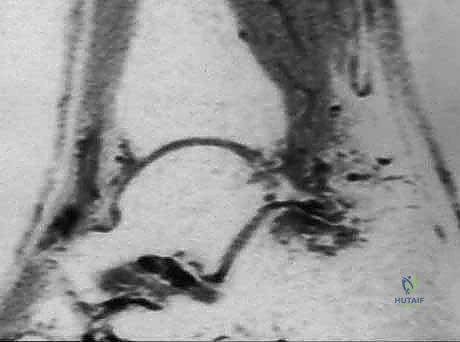

- الحقن الموضعي الموجه (Ultrasound-Guided Injections):

إذا لم يستجب المريض للأدوية والعلاج الطبيعي، يتدخل الدكتور هطيف باستخدام الحقن الموضعي. يتم حقن مزيج من الكورتيكوستيرويد (مضاد التهاب قوي) ومخدر موضعي مباشرة في منطقة الانحشار أو حول غمد وتر FHL. لضمان أقصى درجات الدقة والأمان، يتم إجراء هذا الحقن تحت توجيه الموجات فوق الصوتية.

شكل 4: إجراء حقن موضعي في الكاحل الخلفي تحت توجيه الموجات فوق الصوتية لضمان وصول الدواء بدقة متناهية إلى منطقة الالتهاب وتجنب الأعصاب.